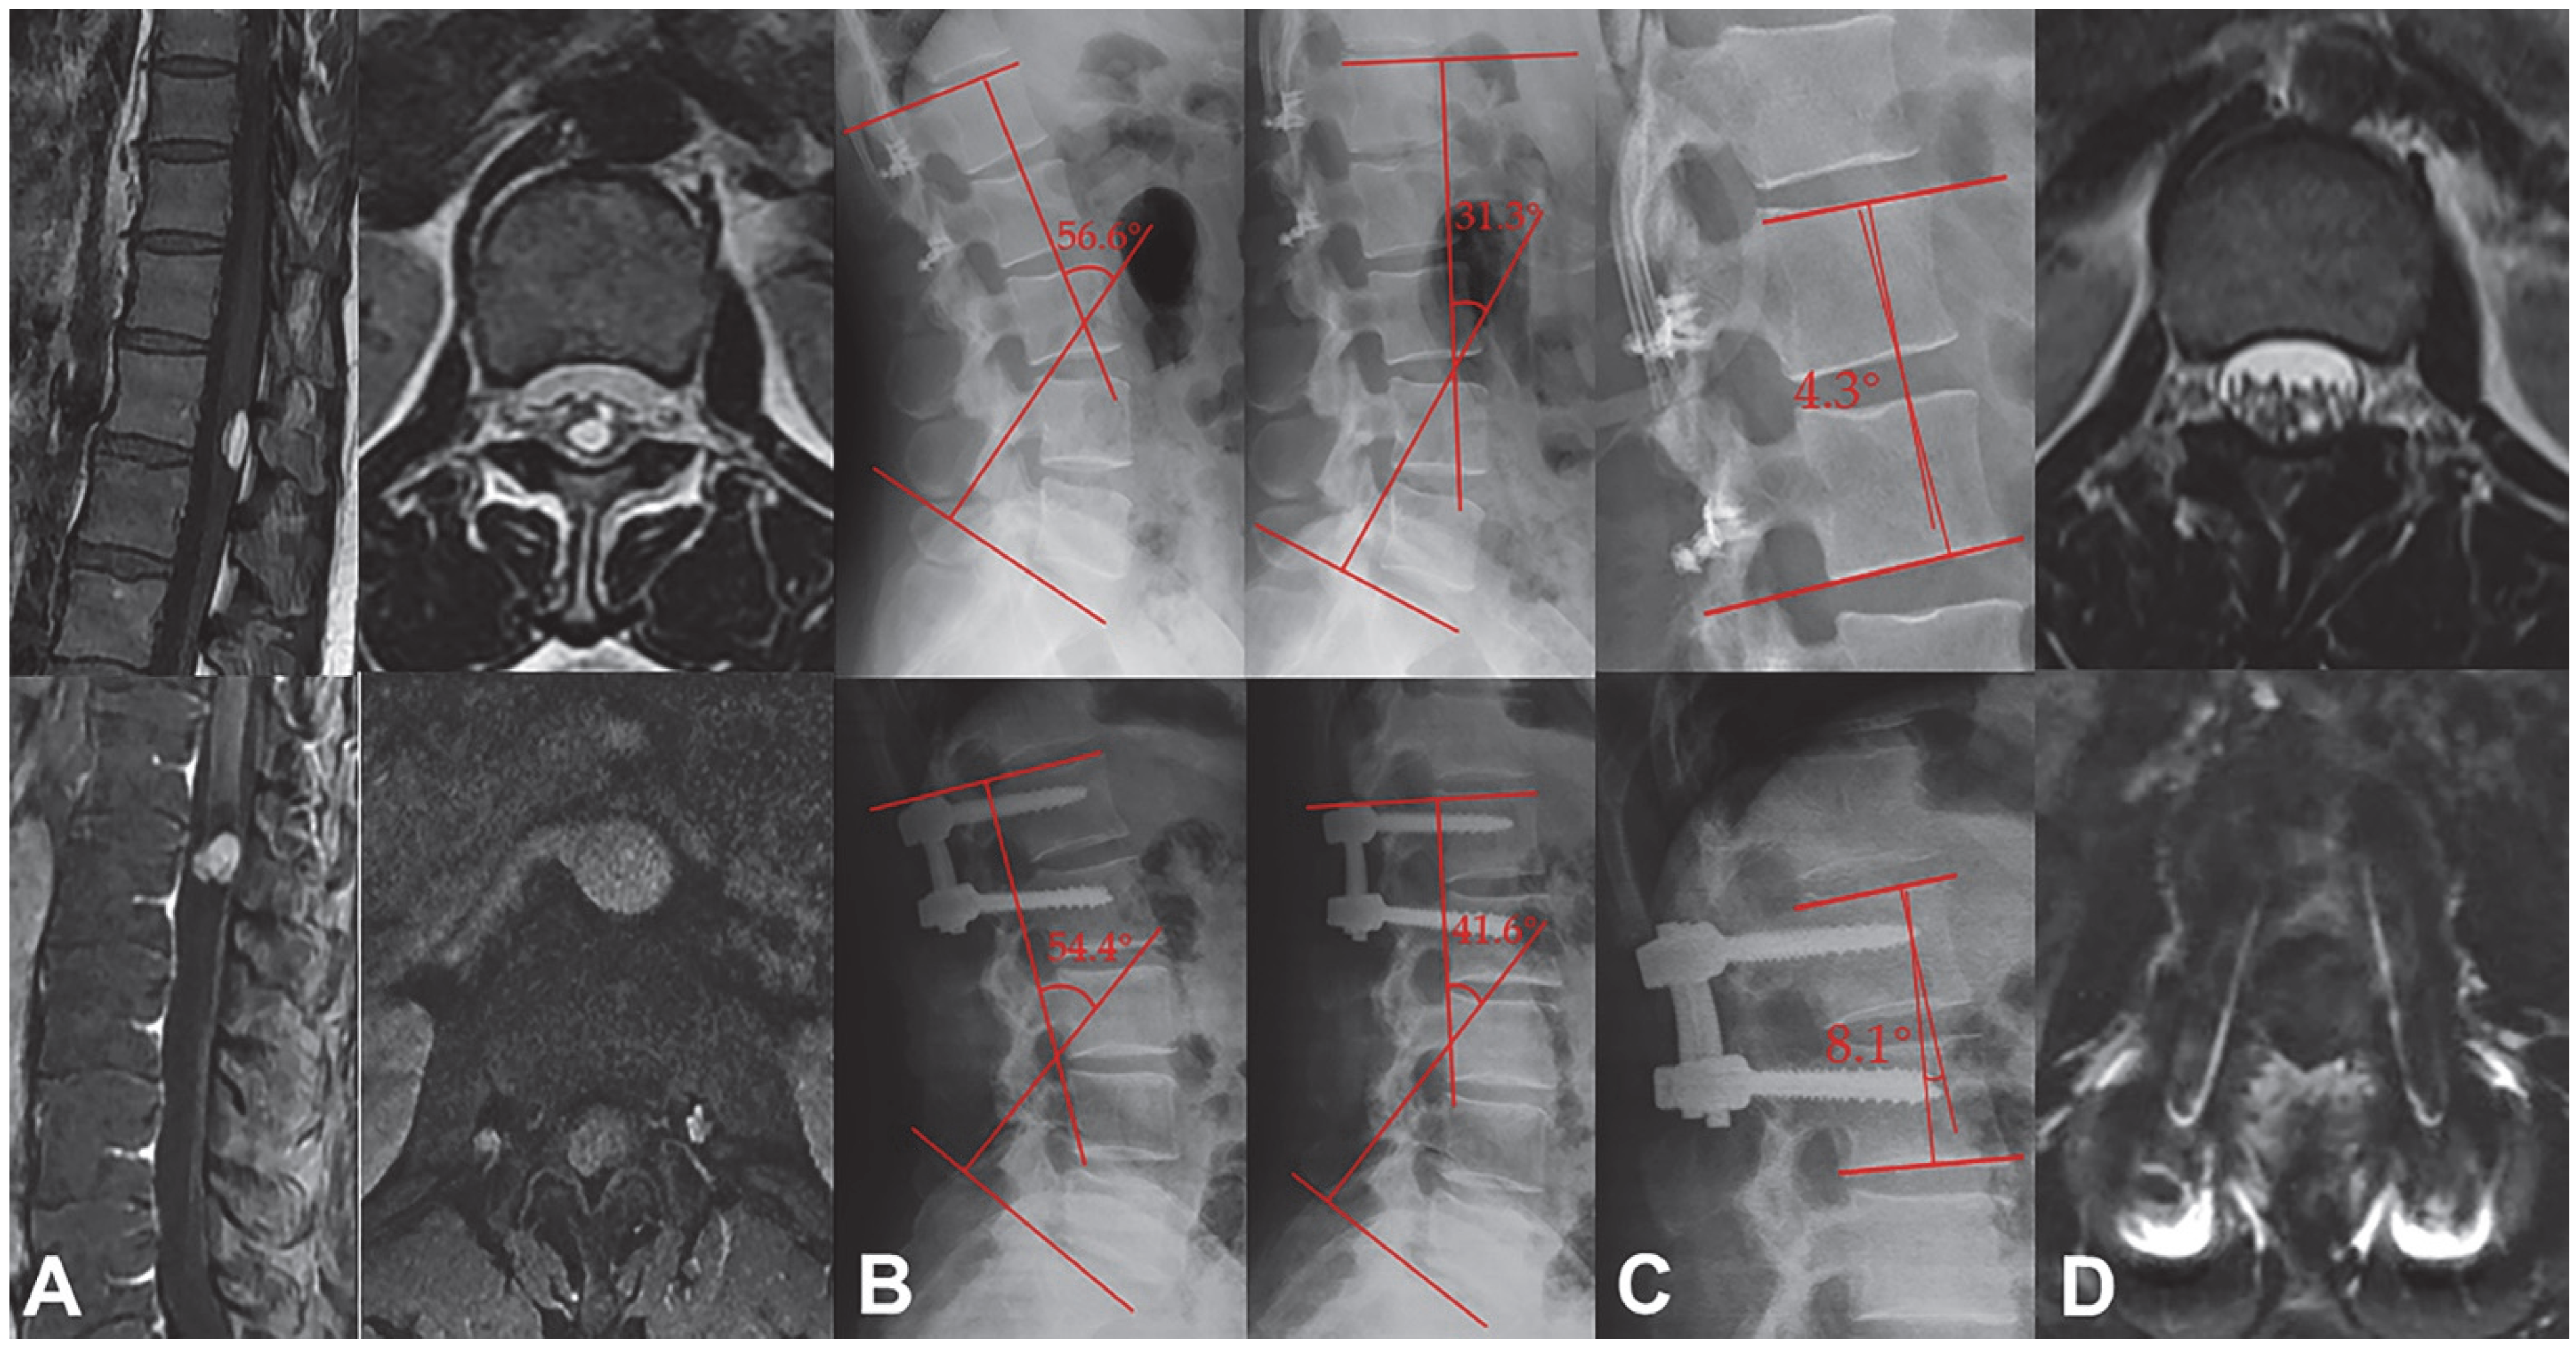

3.1. Larger Spinal ROM and Better Stability in Laminoplasty Group

3.5. Results of the Biomechanical Experiments

| Cobb angle (°) | |||

| Before operation | 9.1 ± 4.8 | 9.7 ± 5.9 | 0.668 |

| 3 months after surgery | 8.1 ± 3.0 | 11.2 ± 6.8 | 0.040 |

| 12 months after surgery | 9.6 ± 4.3 | 12.5 ± 5.3 | 0.034 |

| Laminoplasty (n = 20) | Laminectomy (n = 19) | p | |

|---|---|---|---|

| ROM (°) | 31.6 ± 12.0 | 21.7 ± 11.8 | 0.013 |